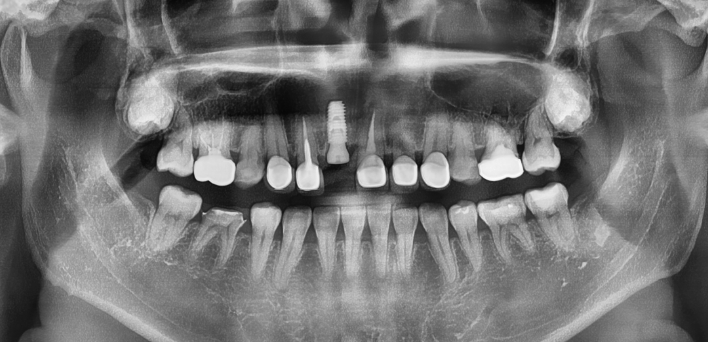

임플란트 케이스

임플란트 Before & After

The seoul dental clinic

※ 더서울치과의원은 의료법을 준수하며 위 케이스는 실제 환자의 동의를 얻은 사례로 치료 전, 후가 동일한 환경에서 촬영되었습니다.

환자 케이스에 따라 부작용이 발생할 수 있습니다. 이 부분은 의료진의 충분한 상담과 체크를 통해 예방하고 줄일 수 있습니다.

[임플란트 부작용] 수술 후 관리가 소홀할 경우 출혈, 주위염 등의 부작용이 발생할 수 있어 구강 위생을 철저히 유지하고, 정기적인 검진을 통해 상태를 점검하는 것이 중요합니다.